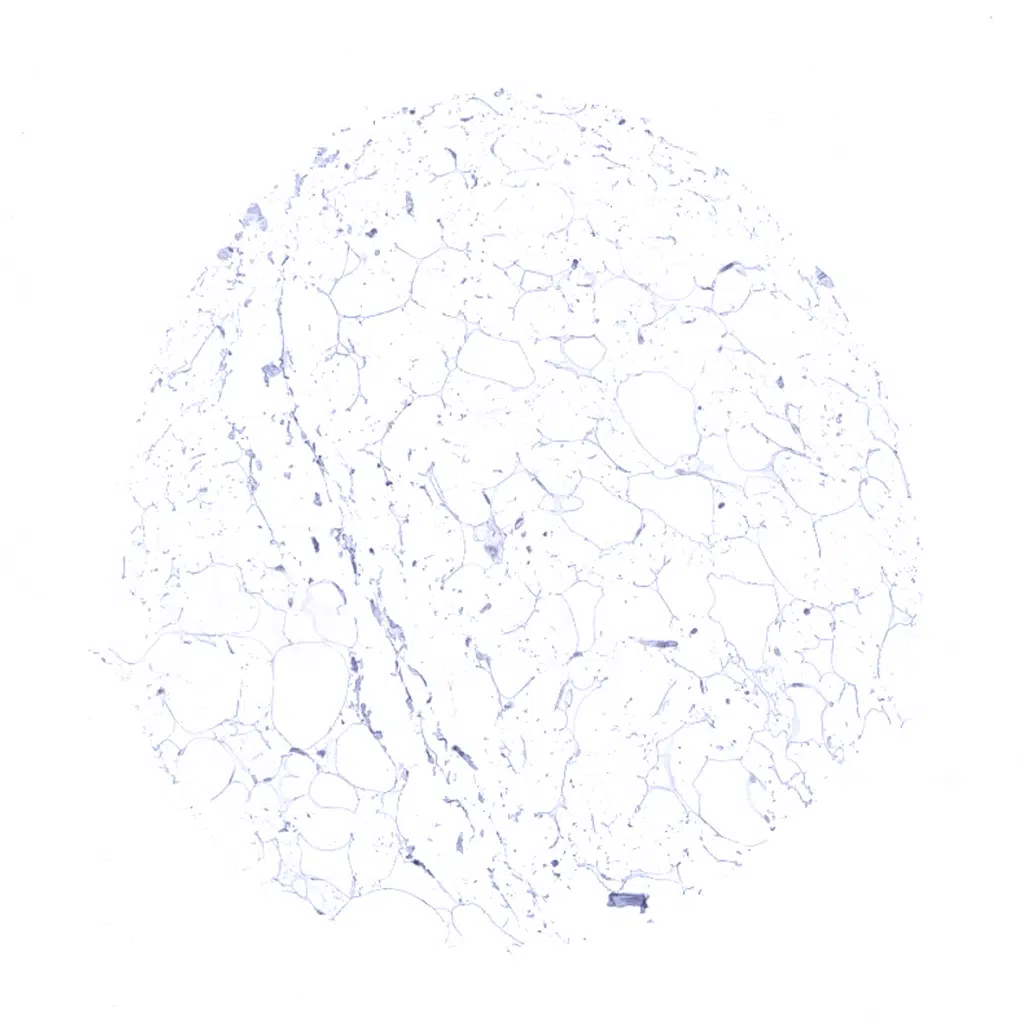

Fat